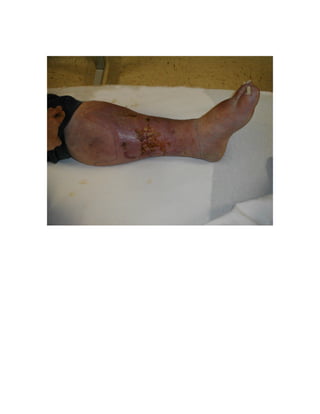

Haemosiderin product of haemoglobin breakdown deposited in the skin of

the lower legs following subcutaneous extravasation of blood due to venous

insufficiency.